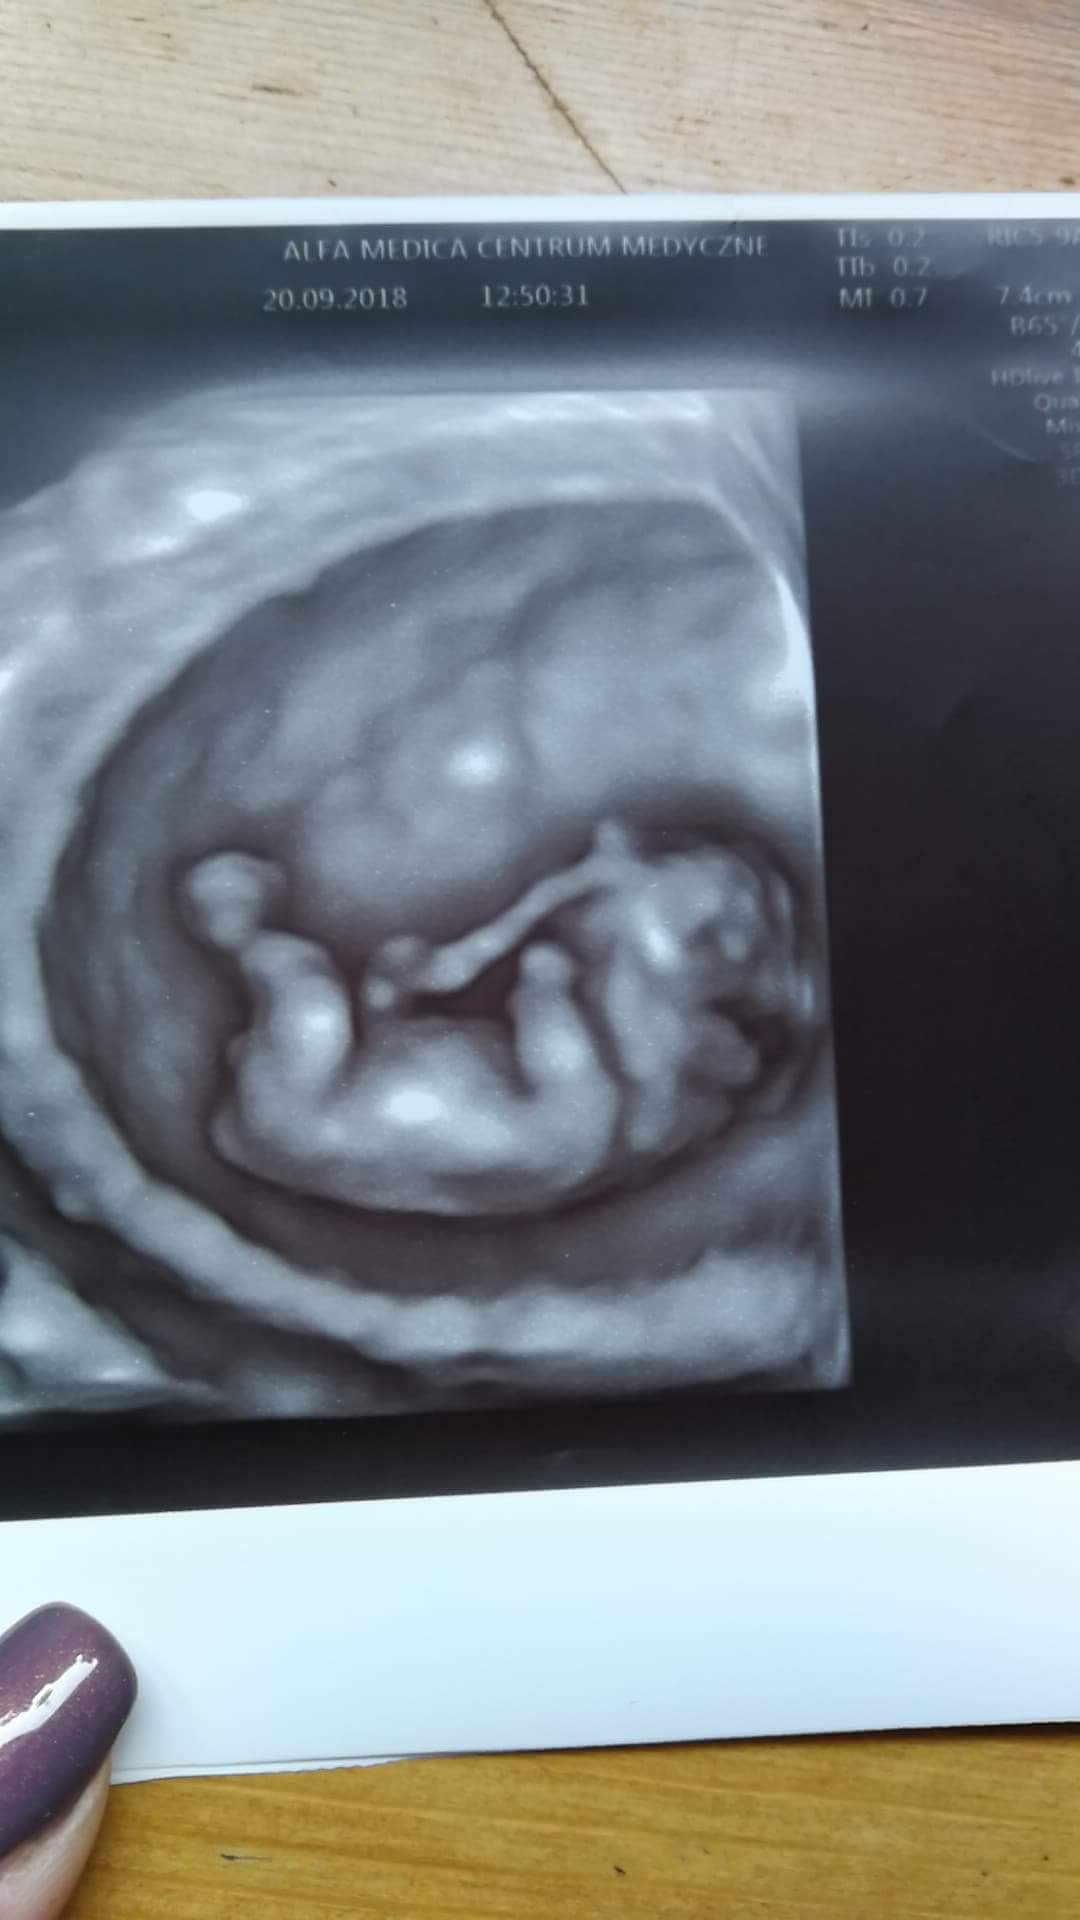

hej :) kamień spadł mi z serca! Po krwiaku nie ma już śladu, dzieciatko ma 4cm, prenatalne za 3 tyg. Doktor chciał żeby nam się lepiej pokazał i troche go powkurzal maluch zaczął tak fikac machać tymi rączkami nóżkami... Ze łzy leciały samoistnie. Niesamowita technologia :) według OM 10+1, według usg 11. Uffff :) dalej mam brać duphaston.